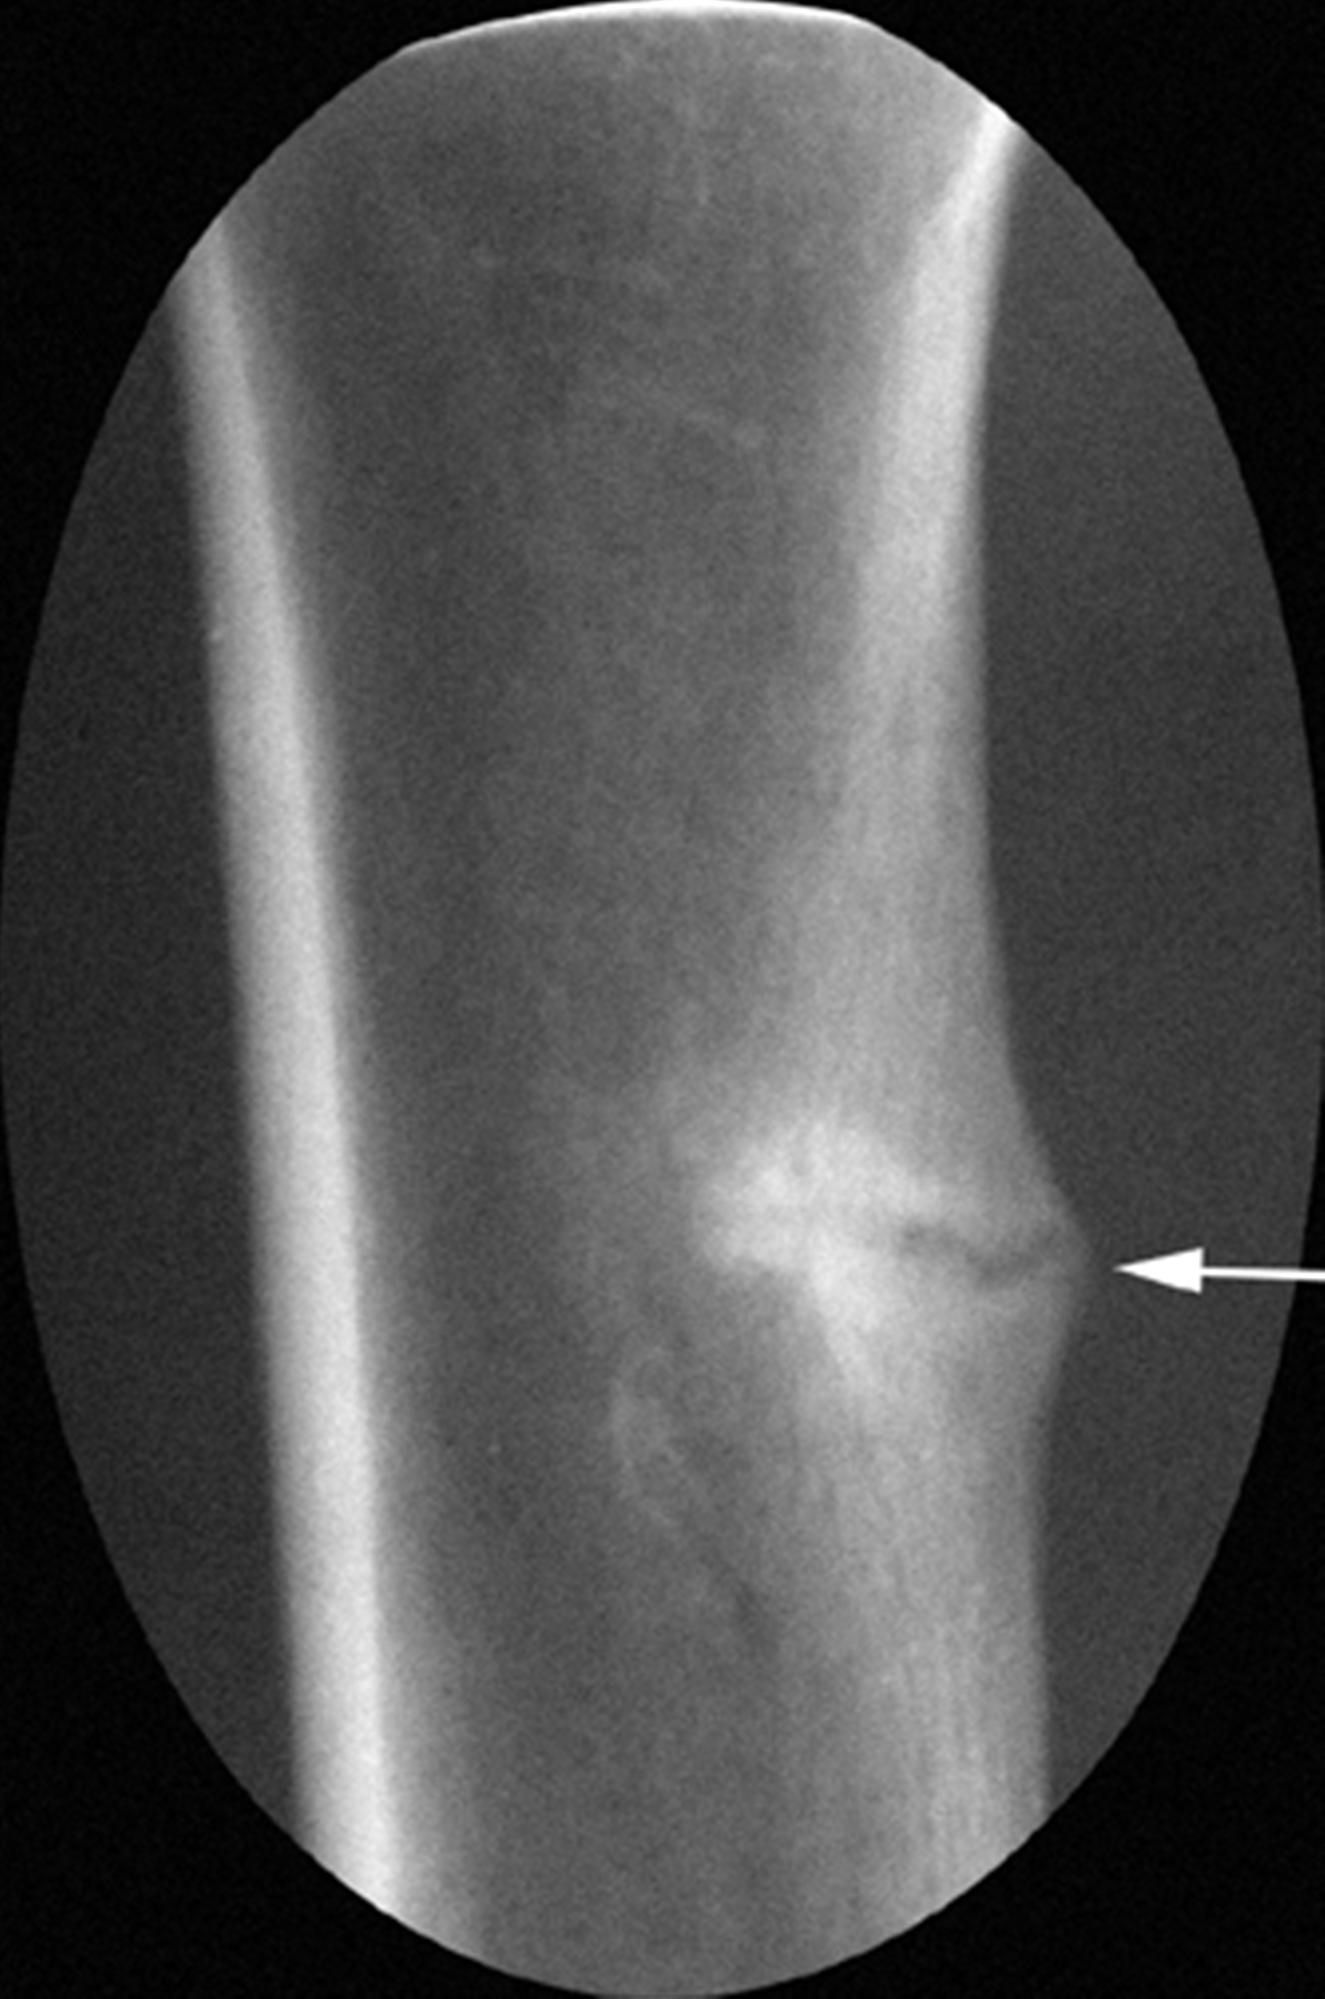

Looser zone Image Looser Zones Radiology Learn about the radiological signs of osteomalacia, paget's disease, and neuropathic arthropathy, which are metabolic diseases affecting the bones and joints. Osteomalacia is the result of impaired mineralization of newly formed osteoid, which leads to characteristic looser zones. Fatigue fractures in femur predominantly affect its cancellous bone dominant parts such as metaphysis, neck and intercondylar. Looser zones, also known as. Looser Zones Radiology.

From www.cancerjournal.net